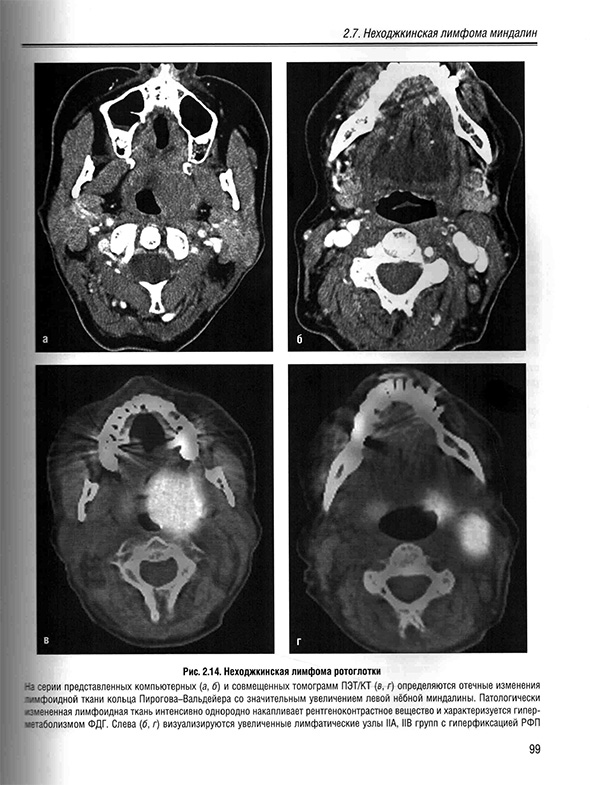

2.7. Неходжкинская лимфома миндалин